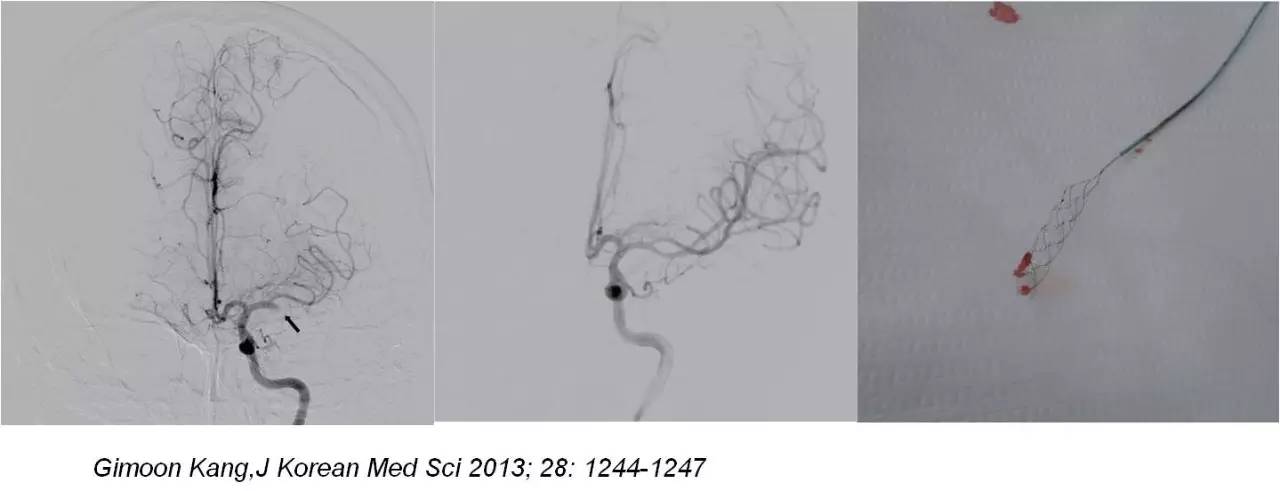

病例二

》男性,47岁,SIE;

》UCG:主动脉瓣关闭不全,赘生物;

》突发言语不能、右侧肢体活动不能;

》查体:运动性失语,右侧肌张力低,右侧肌力0级,右侧巴氏征阳性 。NIHSS评分18分;

》CT:颅内未见出血;

》DSA:左侧大脑中动脉闭塞。

术前

术后

》意识清楚,言语流利,四肢活动自如;

》四肢肌力Ⅴ级;

》术后24小时NIHSS评分:0分;

》5天后主动脉换瓣术;

》90天mRS评分0分。